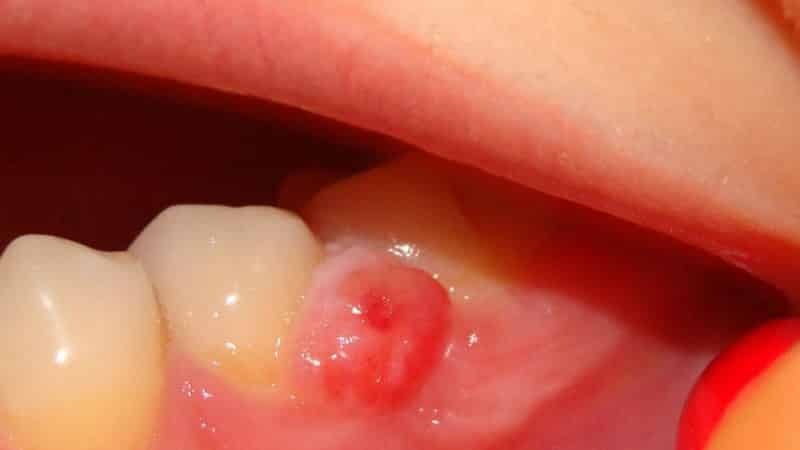

Почервоніння, набряклість, болючість ясна при натисканні або іншому функціональному навантаженні – перші ознаки нариву

Наривами на яснах називають аномальні утворення, що виникають внаслідок запалення, розплавлення, нагноєння м'яких тканин.

Фурункули та абсцеси насамперед заявляють про себе такими проявами:

- припухлість, почервоніння потерпілої ясна;

- на яснах з'являється білий гнійник;